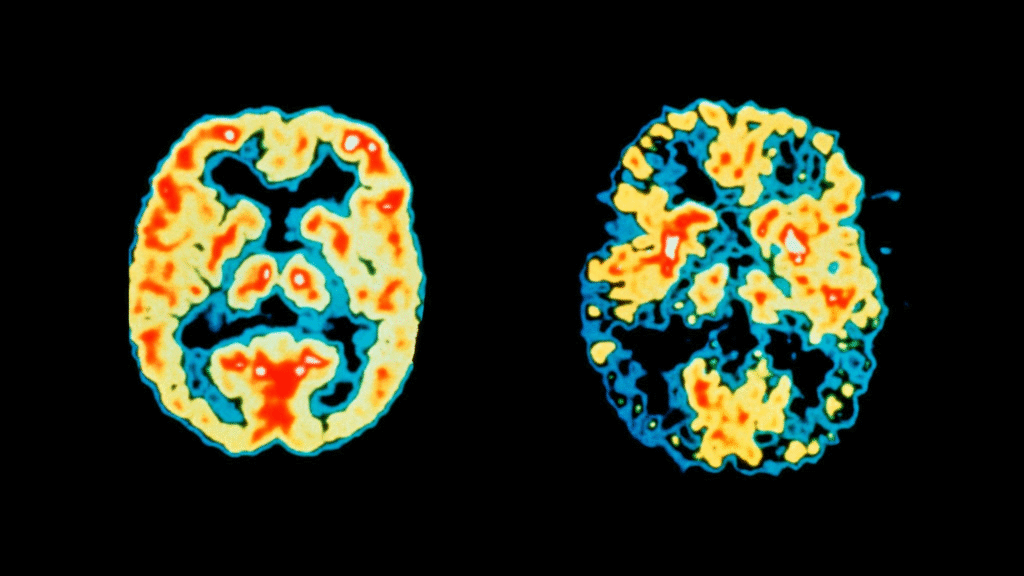

Reduced Blood Flow and Brain Activity

PET scans showing metabolic activity of a normal (left) versus an Alzheimer’s (right) brain. The colors show an activity heatmap from low (blue/black) to high (red/yellow). The Alzheimer’s brain has reduced function and blood flow.